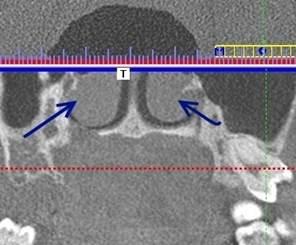

Рис. 4. Компьютерная томограмма пациента. Стрелками указаны большие воздушные буллы средних носовых раковин.

При искривлении носовой перегородки вбок у пациентов с объемными образованиями в гайморовых пазухах с обеих сторон были выявлены большие воздушные буллы средней носовой раковины.